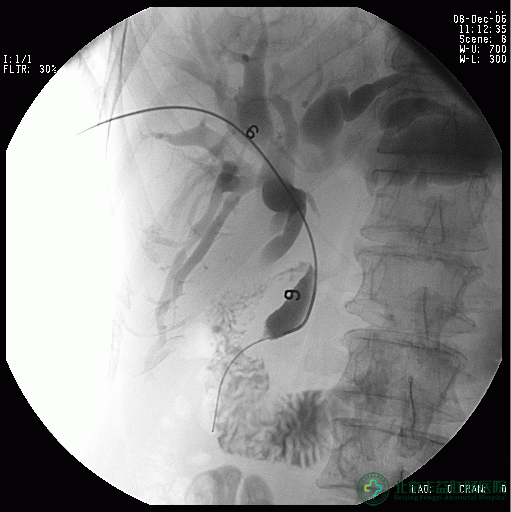

肠瘘的治疗措施